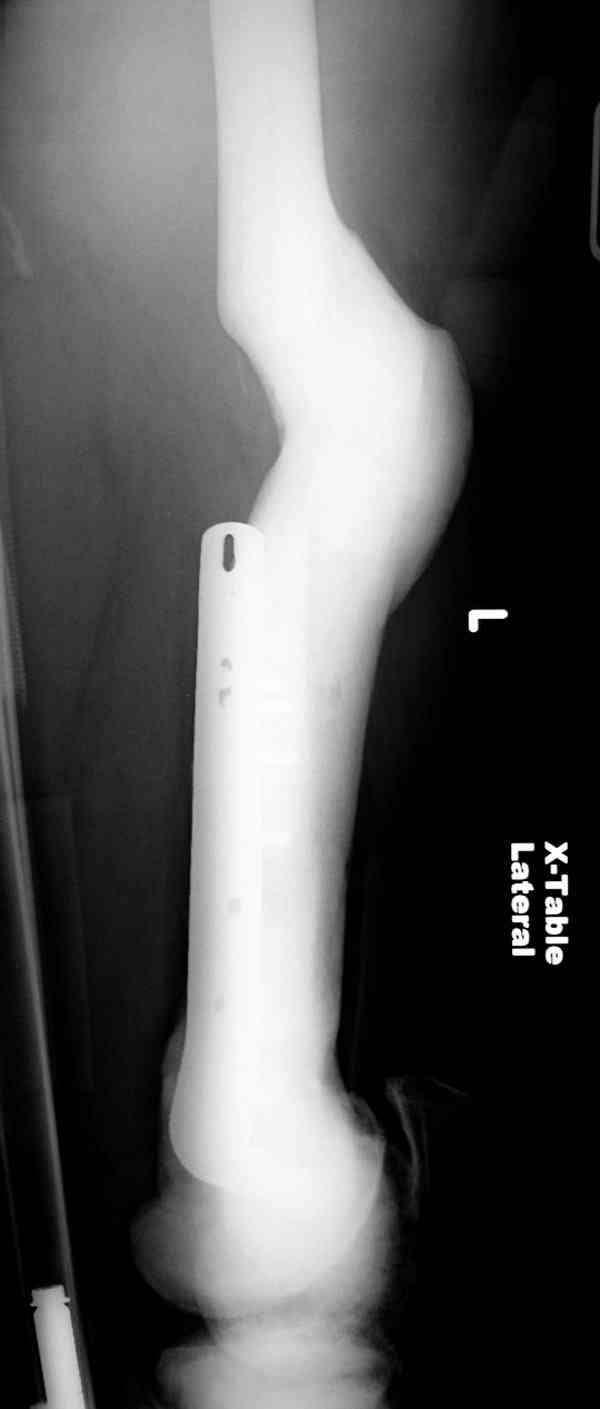

Здесь у меня дополнительные снимки с большим разрешением и в разных режимах, а то те дигитал снимки совсем очень блеклые, может, эти изображени изменят выбор тактики

После неудачной попытки скелетного вытяжения в первом мед.учреждении, после осмотра снимков и изучения истории, поставили диагноз “Остеопетроз” или мраморная болезнь, редкая наследственная костная паталогия, где имеется нарушение формации остеокластов.

Конечно, было бы идеальным применение интрамедуллярного остеосинтеза, но учитывая прежний собственный опыт (лечил перелом бедра) и

публикации, предупреждающие о трудностях при обработке кости (иногда из-за неподготовленности инструментария результатом была неадекватная фиксация перелома, или перенос операции из-за фактора усталости оперирующего персонала), решили применить пластину (и в этом же случае был выбран Synthes plate, так что представитель за два дня

зароботал... на десерт тоже).

Заказаны были дополнительные различные дрели, и на следующий день, усиленной бригадой, больного прооперировали, потратив на каждое отверстие около 25-35 минут, хотя сверлили с охлаждением по нарастающей по диаметру сверл и с их заменой каждые 2 мм сверления.

Теперь стоит задача со сращением перелома, из-за отсутствия литературных данных по применению костных стимуляторов при остеопетрозе, и не зная как поведет в этой среде Grafton, все таки надеюсь, что даст толчок к стимуляцию, решил применить пастообразную деминерализованную костную матрицу, расположив спереди между отломками.